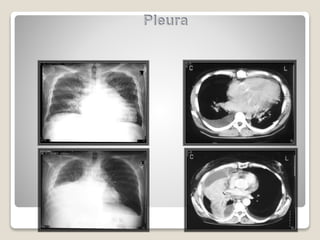

Tomografia de

tórax

• Diferencial comAbscesso Pulmonar

• Coleção Mediastinal

• Espessamento Pleural e Atenuação da Gordura Mediastinal  Sugerem

Empiema

Pearson. Thoracic Surgery,Texxtbokk 7 edition; 2014